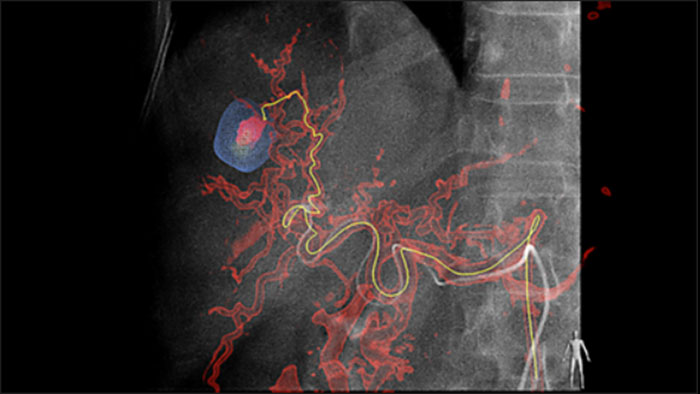

La solución de Detección Automática de vasos Alimentadores puede mejorar significativamente la detección de arterias dependientes. EmboGuide le ayuda a maximizar la eficacia de sus procedimientos TACE, ya que potencialmente mejora su sensibilidad, reduce los falsos positivos y maximiza el acuerdo entre lectores1. EmboGuide también proporciona una guía 3D en vivo eficiente y basada en el flujo de trabajo con detección automática de vasos alimentadores1.

La adopción de técnicas de quimio/radioembolización como TACE y SIRT impulsa la necesidad de estandarización y eficiencia. Caso tras caso, debe localizar de manera confiable y consistente los tumores, identificar todos los vasos dependientes y planificar /ejecutar el enfoque intervencionista apropiado. Nuestra solución de Detección Automática de vasos Alimentadores puede mejorar significativamente la detección de arterias dependientes en comparación con el uso de CT de haz cónico solo. EmboGuide le ayuda a maximizar la eficacia de sus procedimientos TACE, ya que potencialmente mejora su sensibilidad, reduce los falsos positivos y maximiza el acuerdo entre lectores.1

SmartCT Soft Tissue ofrece una técnica de adquisición de CT de haz cónico (CBCT) aumentada con guía paso a paso, visualización 3D avanzada y herramientas de medición; todo accesible en el módulo de pantalla táctil en la mesa.